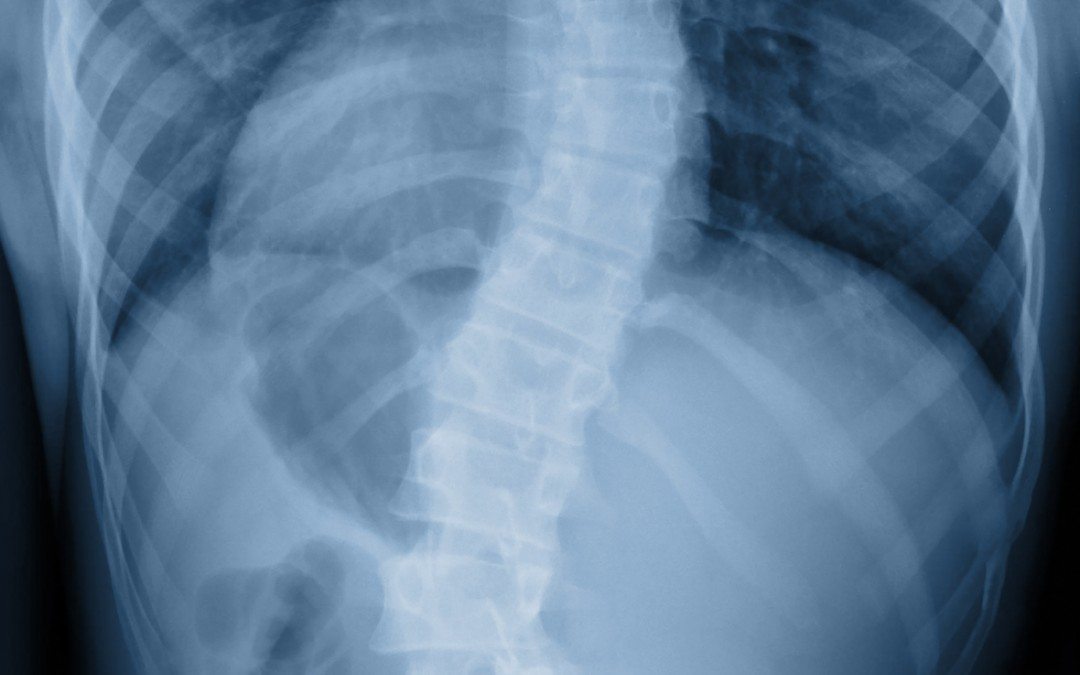

Scoliose de l’adolescent : L’imagerie permet de préciser les caractéristiques de la courbure

La scoliose idiopathique de l’adolescent est une déformation tridimensionnelle du rachis qui apparaît pendant la période de croissance en dehors de tout contexte pathologique.

L’évaluation clinique doit être méthodique incluant un examen du rachis, un examen général et l’appréciation de la croissance. Son objectif serait de confirmer le caractère idiopathique de la scoliose et d’éliminer d’éventuelles complications. L’imagerie permet de préciser le siège de la courbure, la mesurer ainsi que le degré de la rotation, d’éliminer une anomalie morphologique et d’évaluer la croissance résiduelle.

Le traitement fait appel à différents moyens allant de la surveillance clinique et radiologique à la chirurgie en passant par les différents corsets. La rééducation spécifique constitue la première étape du traitement pour prévenir la progression de la déformation, elle doit être initiée par un kinésithérapeute puis poursuivie en autoprogramme.

Quelle que soit l’angulation de la scoliose, quel que soit l’âge de l’enfant ; l’enjeu de la prise en charge est d’aboutir en fin de période de croissance à une déformation scoliotique modérée, compatible avec une vie active normale à l’âge adulte.